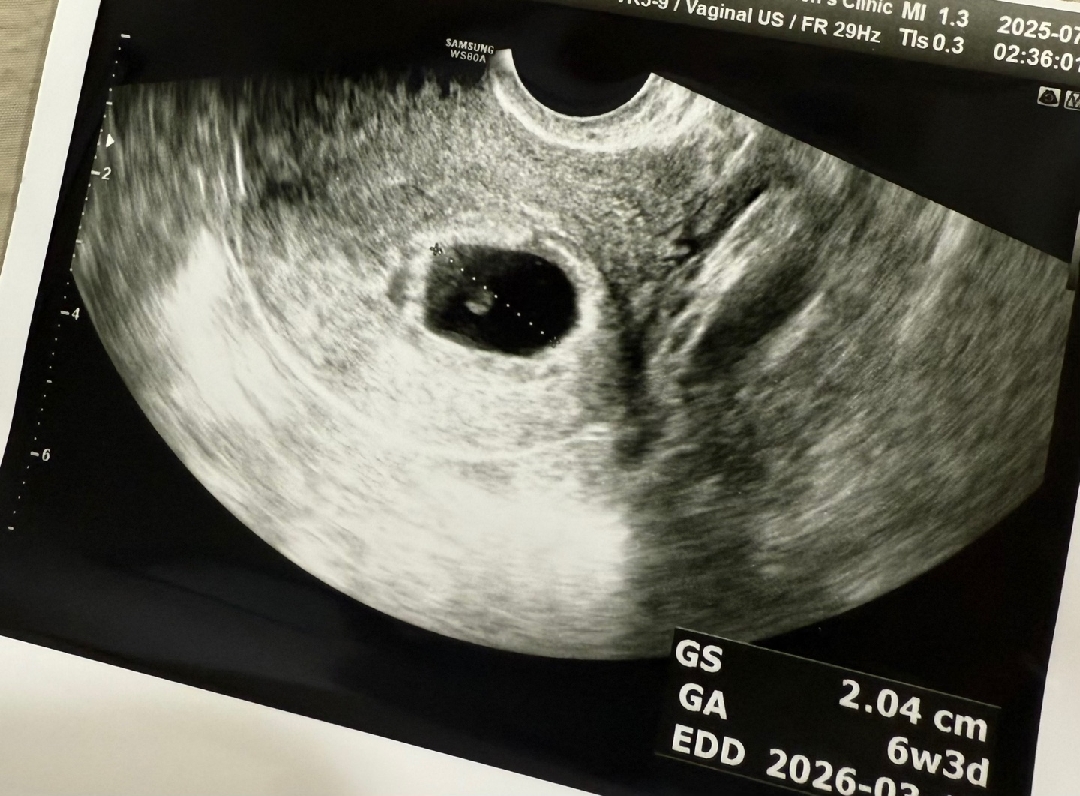

시험관 6주 3일차

안녕하세요. 시험관 3일배아 했고 오늘 6주 3일차인데 심장소리 들으러 갔는데 애기집 크기 좋고 난황도 좋다고 했는데 애기가 안 보인대요... 다음주에 다시 보자고 하셨는데 다음주에 애기 볼 가능성 있을까요..?